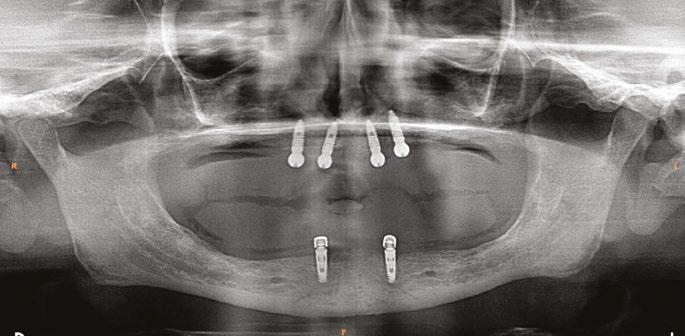

A 59-year-old male reported to the dental office with missing maxillary teeth due to poor oral hygiene. Treatment planning was done for all on four implant placements followed by prosthesis. A complete medical history was obtained and was negative for any significant medical problems. The patient denied being allergic to any medication as well. The patient agreed to the implant placement and was advised to have an orthopantomogram (Figure 1).

on the crest of the ridge in the region of teeth Nos. 15-25. While creating the incision, bleeding was noticed in the region of tooth No. 15 which intensified during the flap reflection (Figure 2). Bleeding was pulsatile, indicating an arterial bleed. Initially attempts to control bleeding included a pressure pack and ice pack, and the bleeder was isolated, and the vessel ligated (Figure 3). The bleeding could be controlled, and the procedure was completed by placing four Bioner implants (Bioner, Spain), size 4/10 mm. Sutures were placed, and patient was kept on basic medication for pain and infection control. Immediately after the surgery, the patient was advised to get a CBCT. As shown in Figure 4, a coronal view and Figure 4B (yellow arrows), the position of the artery can be seen.

In the follow-up sessions, the patient was comfortable, but did complain of mild swelling which subsided within 4-5 days. A post-op CBCT showed excellent recovery, bone width, and proper implant placement (Figure 5).

Figure 1: Pre-op panoramic radiograph Figure 2 (left): Alveolar antral artery (AAA). Figure 3 (center): The artery has been ligated with suture. Figures 4A and 4B (right): CBCT post-implant placement and position of the artery coronally (top). 4B. Showing the position of alveolar antral artery (AAA) in relation to implant placement as indicated by the yellow arrows (bottom)

Figure 5: Panoramic radiograph following implant placement